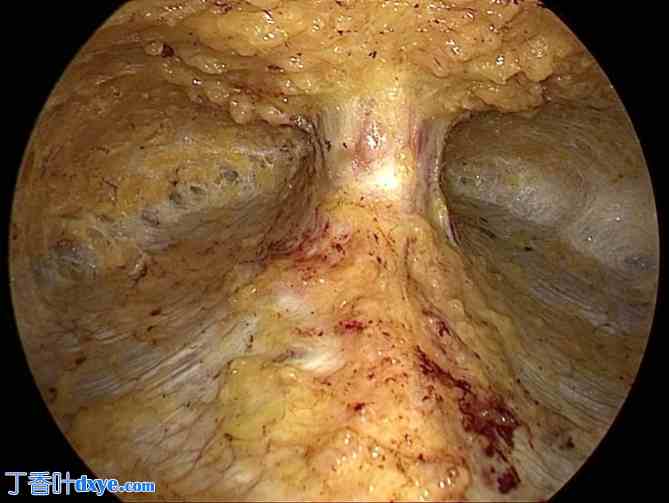

图3.

3.jpg

解剖后的疝囊,形似花瓶。